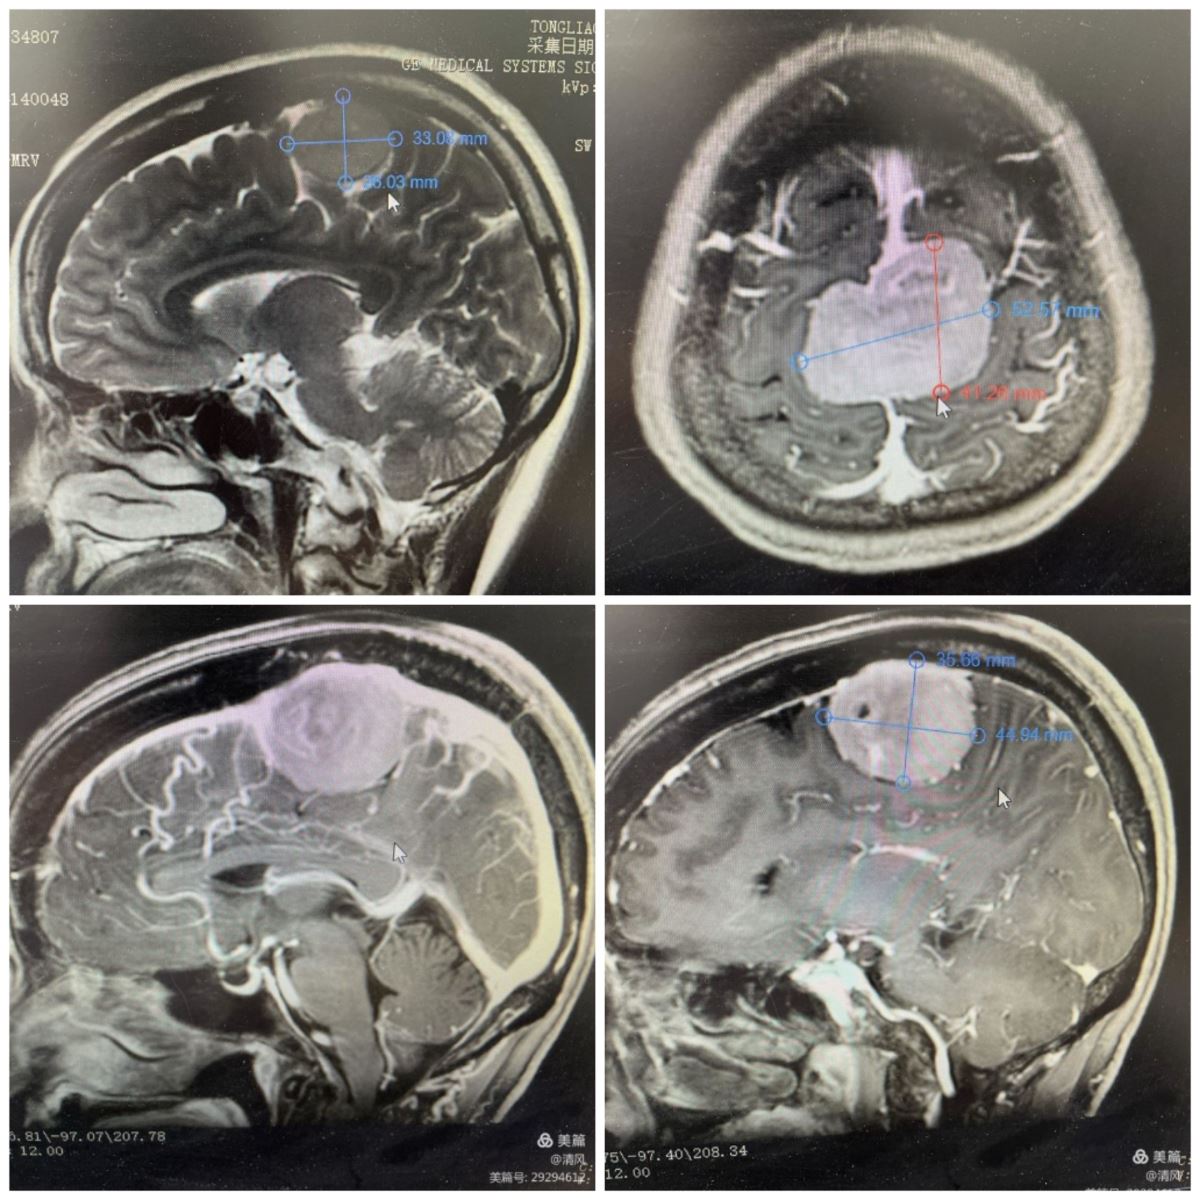

患者女性,55岁,颅内占位性病变10余年。近半年来,患者右上肢出现间断性麻木,到我院西院区神经外科就诊。经查体,患者生命体征平稳,神清语明,右上肢感觉稍减退。完善相关检查后,头颅核磁提示:跨矢状窦1/3占位,肿瘤血运丰富,与周围引流静脉关系密切。用3D软件行肿瘤与MRV重建,显示肿瘤与矢状窦、引流静脉关系密切。

该病例患者,肿瘤长入矢状窦,且矢状窦未完全闭塞,手术力求能全切肿瘤,这样既能保证矢状窦通畅,又对周围功能区脑组织不构成损伤,不影响患者功能,让患者完整回归社会。秦义民主任带领全科人员,充分讨论,制定周密治疗计划、拟定详细手术方案及术中各项预案。秦主任和陈林、郭学富医生经过显微镜下长达12小时的手术,采用冠状切口,跨窦骨瓣开颅,术中见肿瘤横跨矢状窦,血运丰富,浸透大脑镰,长入矢状窦,行瘤内切除减压后,沿肿瘤边界小心分离切除肿瘤,最后打开矢状窦,切除长入矢状窦肿瘤,修补矢状窦,完全切除肿瘤。术后患者切口血运佳,愈合良好。术后第五天,患者神清语明,双下肢肌力4+级,已能独立行走,恢复良好。